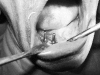

Fig. 10

Permucosal extensions placed in the region of 35 and 45 after 3 1/2 months